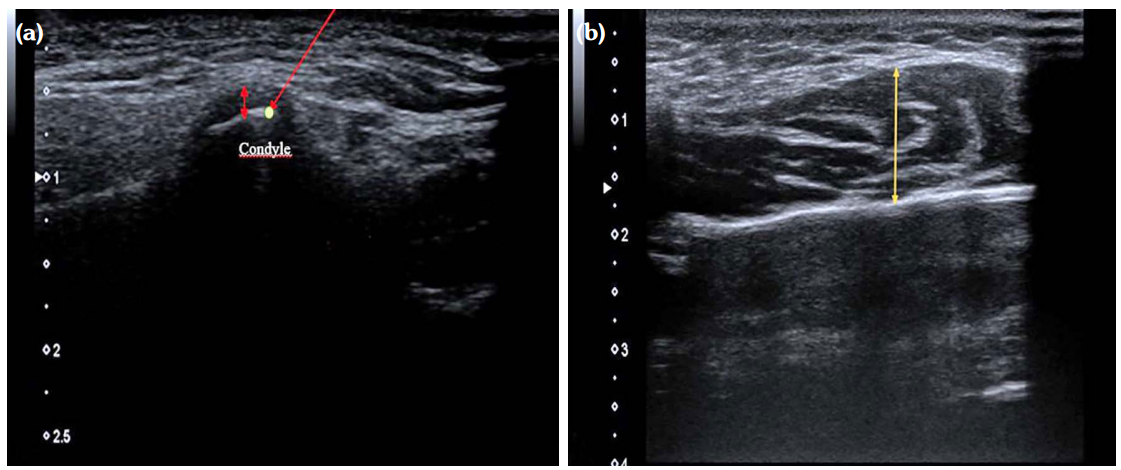

After the thickest place of the muscle was determined by palpating both the right and left masseter muscles, the probe was placed transversely, the mouth was closed and anteroposterior measurement was performed without compression with the probe from the thickest part of the muscle while the muscle was at rest (Figure 2b).

During the USG examination, the effusion displayed as a hypoechoic area in the joint cavity on bilateral TMJ, irregularity on the bone surface, the presence of osteophytes, which are seen as hyperechoic new bone formations with exophytic extension, were evaluated and recorded on the examination form as present or absent. In the TMJ evaluation, flattening and irregularity in bone structures were noted as temporal bone or condyle degeneration.